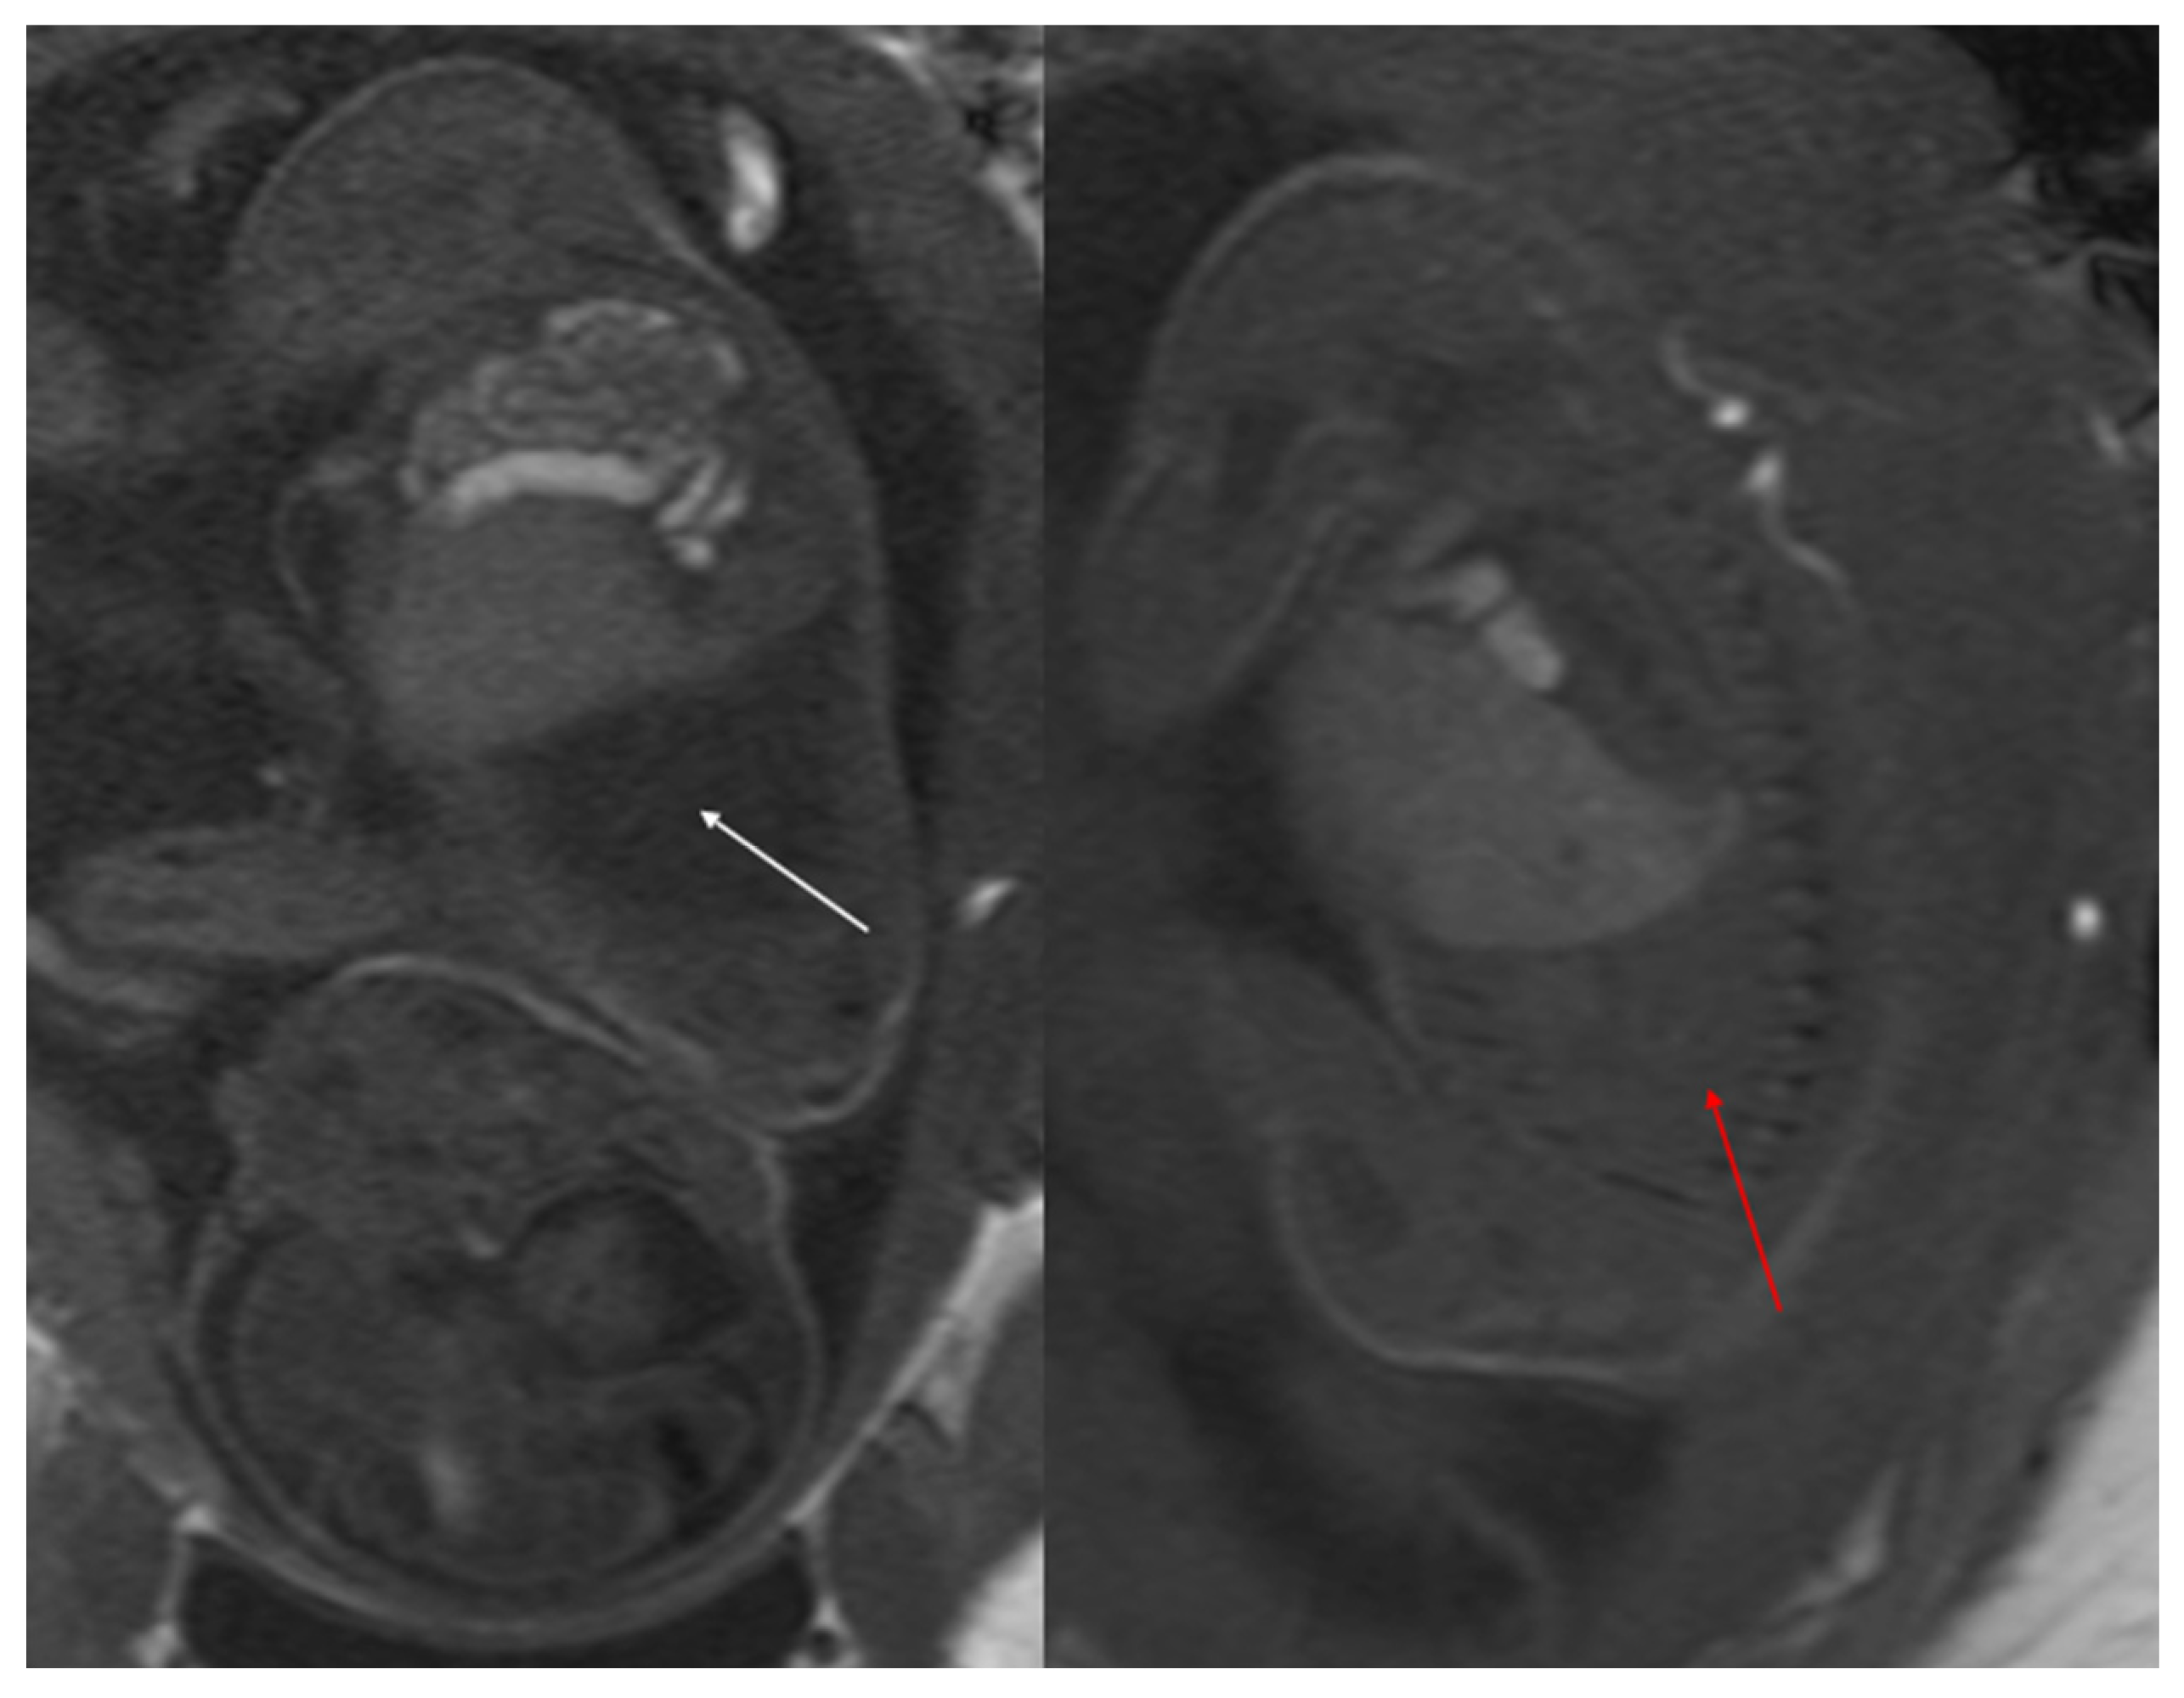

Figure 3. CPAM type III. Coronal T2 HASTE image shows, diffuse hyperintensity of the entire left lung (white arrow), without evidence of recognizable cystic structures. Note the normal intensity of the right lung (red arrow).